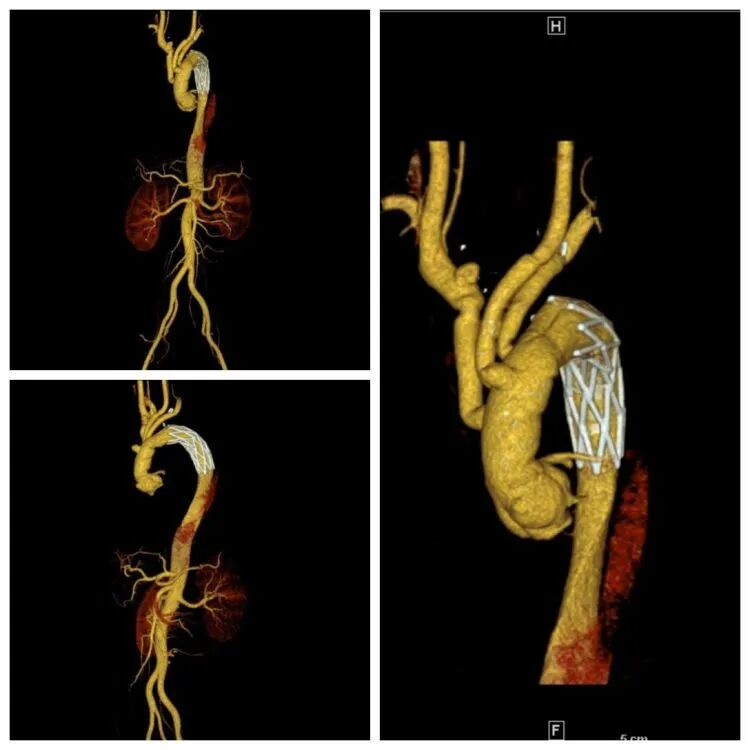

术后复查胸腹主动脉CTA示主动脉形态良好。

术前胸腹主动脉CTA示主动脉夹层(Stanford A型)

术后复查胸腹主动脉CTA示主动脉形态良好,重建的椎动脉通畅。